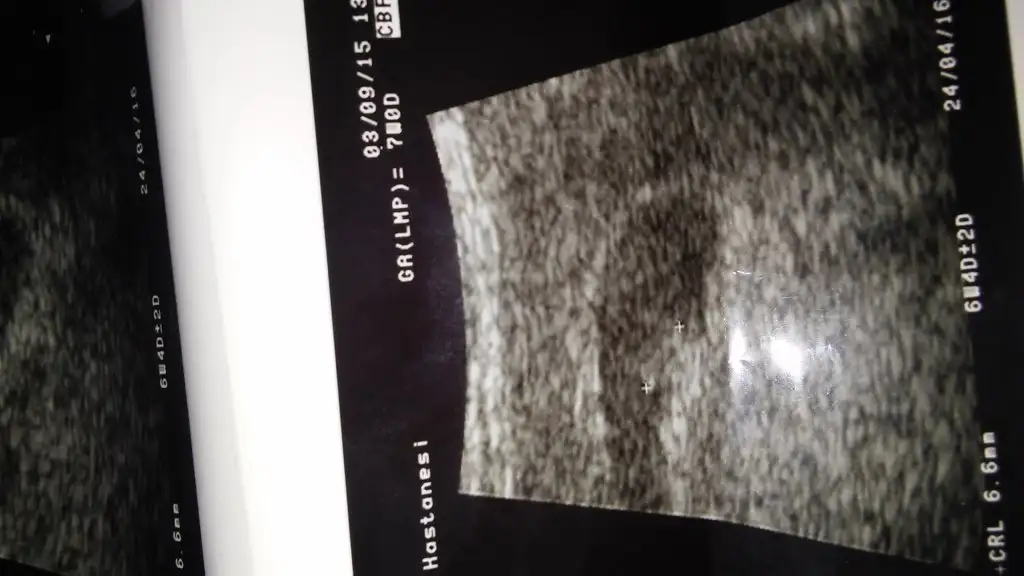

cnm ben usg yı bulamadım nerede? terar yuklesen?7 haftalık canım...

cnm ben usg yı bulamadım nerede? terar yuklesen?

Gijnij çok saol canım benim yorumun için zaten şimdi hiçbişeyin kesinliği yok öyle meraktan bizimkiside yok bu cinsiyet tahmini yok kırmızı lahana testi hepsi meraktan dolayı oyalanmak işte rabbim çocuklarını sana bağişlasın inşallahSinerjik bence keseye göre yorum yapmak çok sağlıklı olmaz ben çok araştırdım kese inan erkek bebektede kız bebektede farklı olabiliyor. Ama yinede bir yorum istersen bebeğin baya belli oluyor ve kafası büyük erkek olma ihtimali var ama asla kesin değil. Nub teorisi daha net olur ozamam daha iyi yorum yaparız sana

Canım nub teorısı dıye bır grup var orda yorum yapıyolar sanırım. Sende hamılelık takvımı yapsana buraya.Bu gruplarda nerde selver kk dami yoksa facedemi? Gormek isterim o usg fotolarini falan...

Çok tesekkur ederim sordum bundan başka 10 haftanın üzerinde yokmuşEylülsıla arkadaşın bebeğinin arkası dönük o yüzden nubu belli değil yorum yapmak yanıltıcı tamamen daha farklı yan durmuş poz varsa onu yükle ona yorum yapalım canım